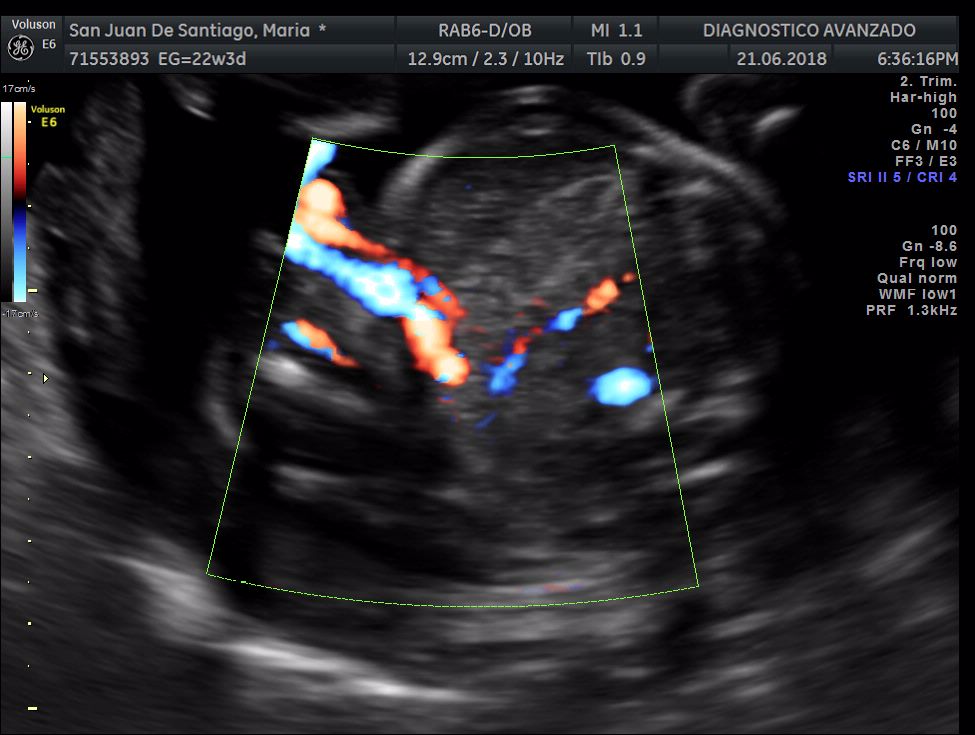

¡Hola a todos! Hoy hemos ido a hacer la tradicional ecografía 3D de la niña, os dejamos todo el material (aunque es un poco demasiado).